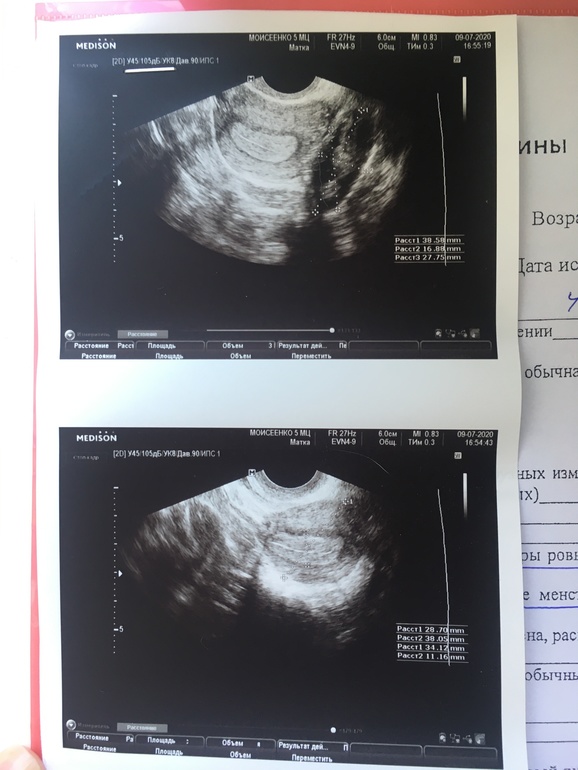

Сходила я на узи, решила посмотреть, была ли овуляция, какой у меня эндометрий после овуляции ну и все в принципе)

Получилось так, что попала только на 9-11 дпо (программы разные даты ставят а по узи не отслеживала ибо это трудно с соим то циклом😂)

Жт не нашла, говорит что скоро месячные

Все верно, М через день-два. ЖТ уже регрессировало в белое тело, прогик обрушился и теперь начнёт отходить эндометрий.

А эндометрий не маловат?

Написано 1,1 мм

Или это именно из-за того что скоро месячные?

Виктория Александровна

Там они видят структуру эндика, что он уже слоится, т.е.отторгается начинает) А ЖТ всегда превращается в БТ, у кого то уже после начала КД, у кого то до, как у вас, у меня так же бывало. А нет ЖТ - значит нет прогестерона и части эстрогена, а они поддерживают 2 фазу и возможную Б. Но Б нет - ЖТ не нужно, организм лучше нас знает как экономить на гормонах😁, просто убирает ЖТ.